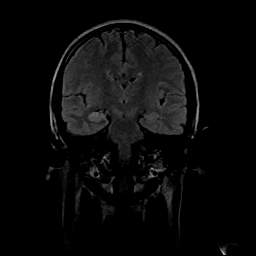

女性,47岁。mri号03027,外伤致头痛9天,抽搐一天,原无类似病史。

右侧海马硬化

右侧海马硬化可能。

双侧海马的信号都有异常。

双侧海马硬化!

颞叶前部萎缩,海马萎缩,t2wi海马高信号,支持海马硬化。

双侧海马硬化.

双侧海马区t1低,t2高信号。为什么都考虑硬化?发病原因?鉴别诊断:炎症,梗塞等能一下子除外吗?